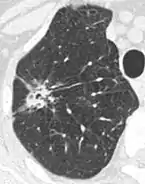

Lobulated nodule.[9]

Spiculated lung nodule.[9]